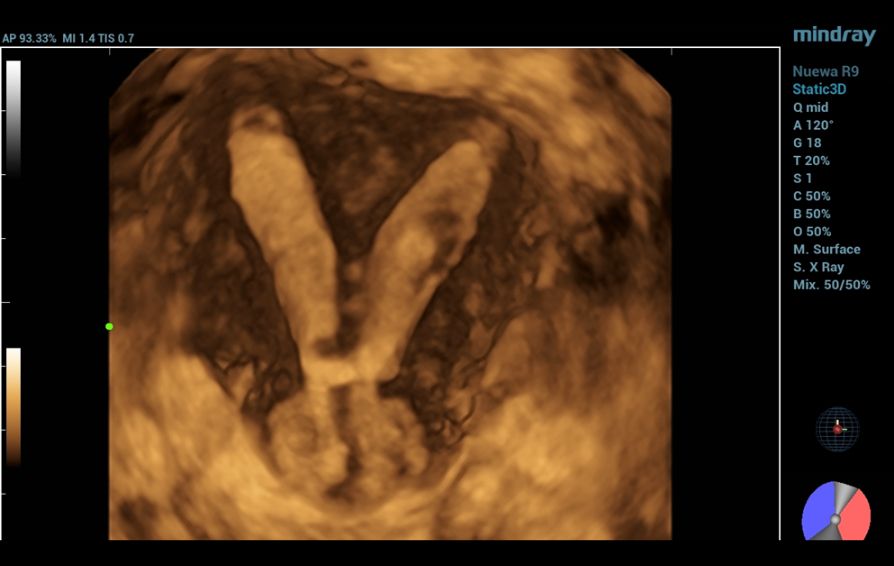

To further assess the anatomy, a 3D ultrasound was conducted, which provided the true coronal view of the uterus. This enabled better visualization of the uterine cavity and external contour, allowing for more accurate classification.

Based on the 3D ultrasound findings, the impression was complete septate uterus with septate cervix.

Furthermore, the application of Smart ERA (Endometrial Receptivity Analysis) enhanced the diagnostic evaluation by providing automated, high-resolution analysis that clearly delineated the septate uterus and septate cervix, thereby supporting the 3D ultrasound findings.

Three-dimensional ultrasonography is now the gold standard for evaluating uterine morphology, offering clear visualization of both the cavity and external contour [7]. In this case, 3D ultrasound accurately identified a complete septate uterus with septate cervix, a diagnosis that could be easily missed with 2D imaging.The addition of Smart ERA provided automated analysis and clearer delineation of the septal structure, enhancing diagnostic precision and reducing operator dependency. Early and accurate detection supports timely reproductive counseling and appropriate management [8].

This case highlights the crucial role of advanced ultrasound techniques—particularly the integration of Smart ERA—in enhancing diagnostic precision.

The automated analysis clearly delineated the septate uterus with septate cervix, reinforcing the 3D findings and supporting accurate classification. Early diagnosis through such technologies is vital in optimizing reproductive outcomes and informing appropriate patient counseling.